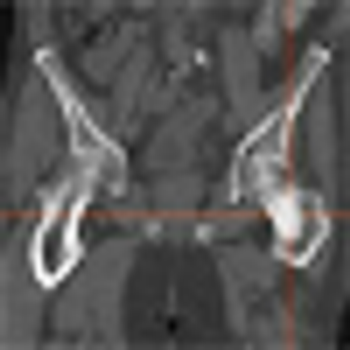

In updated guidelines, the USPSTF concludes that there is still no adequate evidence of a mortality benefit from routine ovarian cancer screening using transvaginal ultrasonography or CA-125 testing.